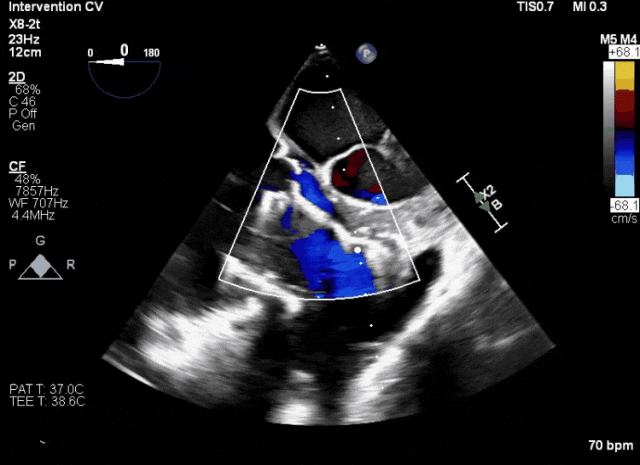

術后超聲顯示人工瓣膜穩定性良好,瓣葉啟閉正常

術前超聲顯示三尖瓣重度反流合并拴系

術中TEE成像困難,偽影干擾